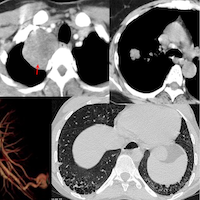

69-yrs old with RA-Sjogren’s overlap ILD with a variant UIP pattern came first in 2022 and then in 2023.

Has increasing cough for 18 months. Questionable fever. Recent weight loss.

Recent CT scan shows a complication.